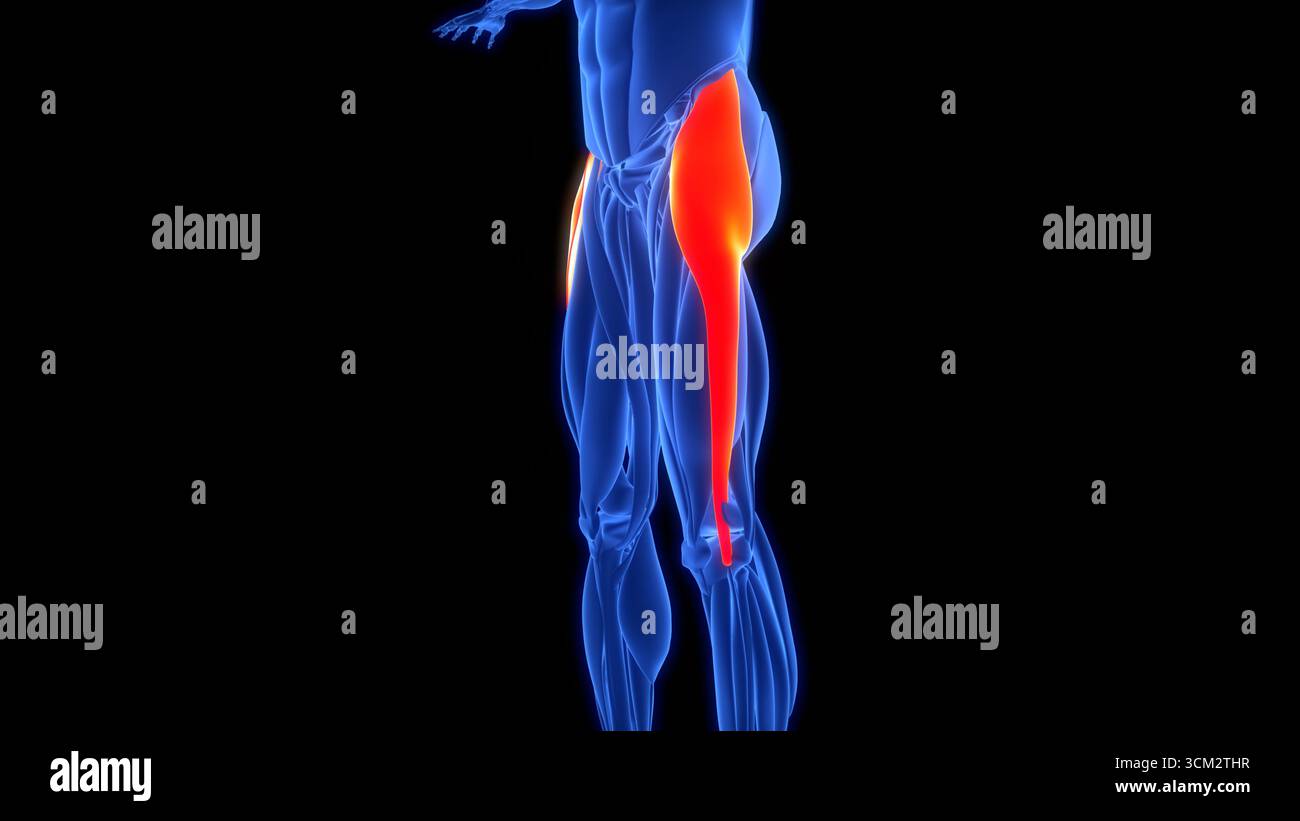

Human Muscular System Leg Muscles Tensor Fasciae Latae Muscles Anatomy Stock Photohttps://www.alamy.com/image-license-details/?v=1https://www.alamy.com/human-muscular-system-leg-muscles-tensor-fasciae-latae-muscles-anatomy-image700771049.html

Human Muscular System Leg Muscles Tensor Fasciae Latae Muscles Anatomy Stock Photohttps://www.alamy.com/image-license-details/?v=1https://www.alamy.com/human-muscular-system-leg-muscles-tensor-fasciae-latae-muscles-anatomy-image700771049.htmlRF3CM2THD–Human Muscular System Leg Muscles Tensor Fasciae Latae Muscles Anatomy